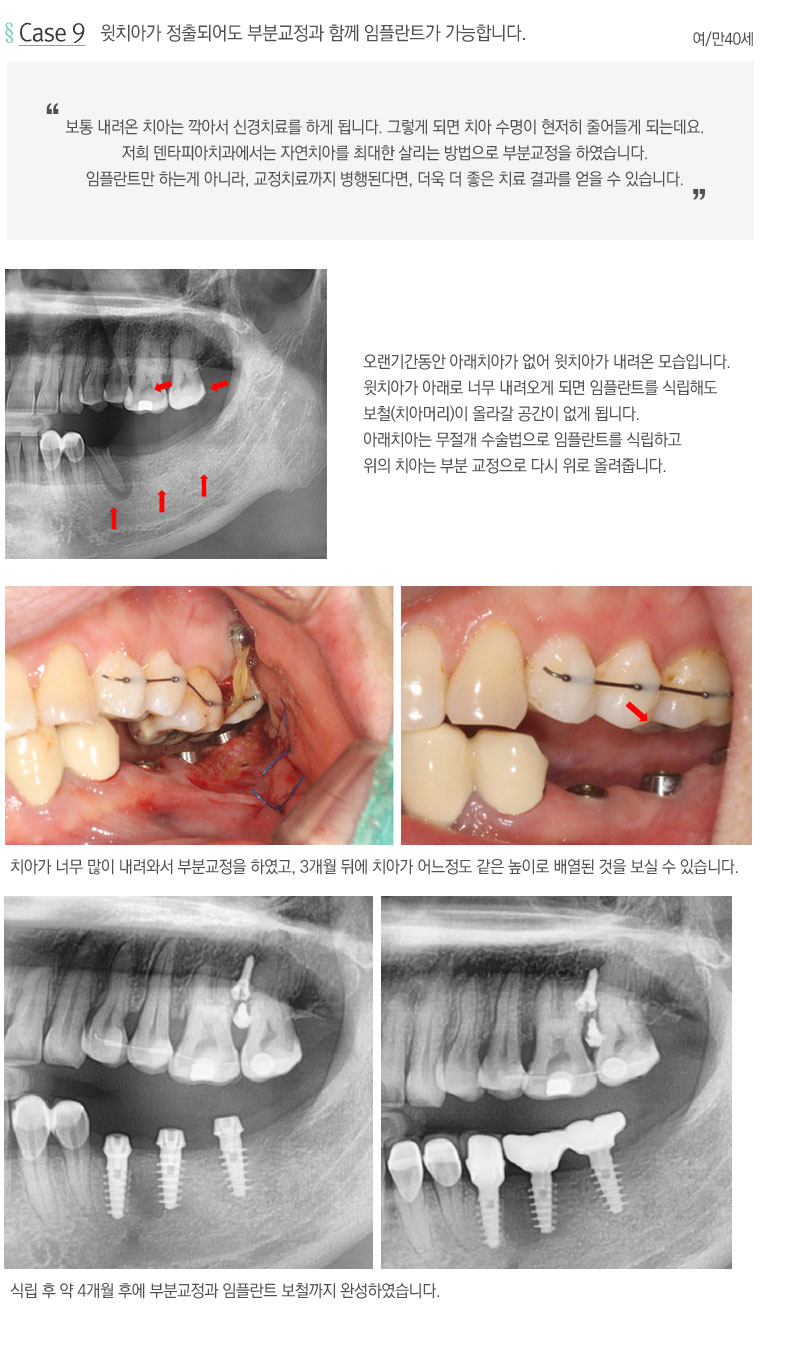

¹«Àý°³ ¼ö¼ú¹ý ½Ã¼ú»ç·Ê

¼÷·ÃµÈ ÀÇ·áÁø°ú dzºÎÇÑ ½Ã¼ú°æÇèÀ» ¹ÙÅÁÀ¸·Î Ä£ÀýÈ÷ ¸ð½Ã°Ú½À´Ï´Ù.

HOME > ÀÓÇöõƮŬ¸®´Ð > ¹«Àý°³ ¼ö¼ú¹ý ½Ã¼ú»ç·Ê